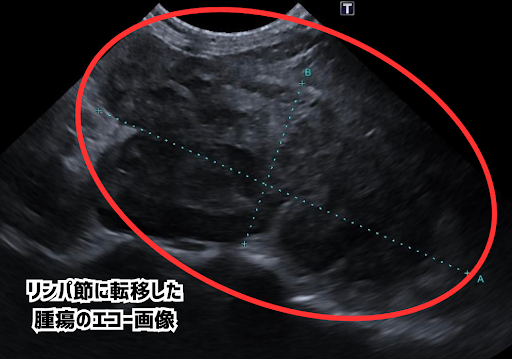

手術前のエコー画像ではリンパ節の転移がみられ、レントゲン画像では腸管が転移した腫瘍により押されているのが分かります。

腫瘍は強く癒着していたため完全な切除ができず、減量手術のみをおこない、その後は飼い主さまと相談の上、抗がん剤治療はおこなわずに経過観察を続けていました。手術後のエコー画像では腫瘍のサイズが小さくなっていること、レントゲン画像では腸管や膀胱が元の位置に戻っていることがわかりました。